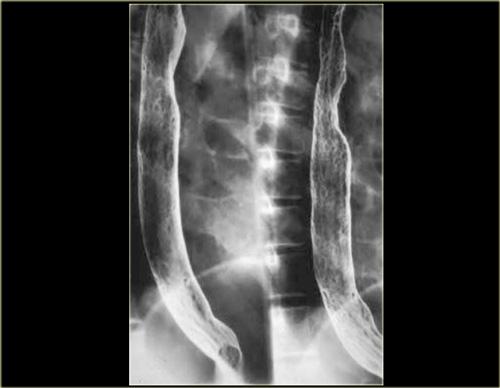

Bên phải là nhiều túi thừa do áp lực (mũi tên) xuất hiện trước khi thực hiện phẫu thuật cắt cơ Heller điều trị co thắt tâm vị (achalasia).

Thực quản mèo: A, B: Cho thấy các nếp ngang mảnh của thực quản; C: Hình ảnh chụp muộn hơn trong quá trình thăm khám không còn thấy các nếp này

Thực quản mèo

Cần phân biệt các nếp đồng tâm mảnh, xuất hiện thoáng qua của thực quản mèo với các nếp dày hơn, gián đoạn, cố định gợi ý sẹo xơ hóa theo chiều dọc do viêm thực quản trào ngược.

Đặc điểm của thực quản mèo bao gồm:

- Các vân ngang do co thắt cơ niêm mạc

- Bình thường ở loài mèo

- Thường thoáng qua và không có ý nghĩa bệnh lý

- Có thể liên quan đến trào ngược dạ dày thực quản hoặc viêm thực quản